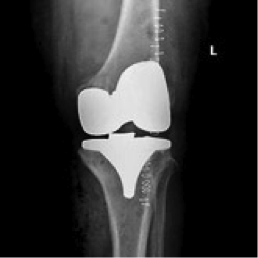

En la mayoría de los pacientes con artrosis severa y generalizada de la rodilla la solución es la implantación de una Prótesis Total. Las prótesis de rodilla habitualmente constan de un componente femoral, un componente tibial y un polietileno entre ambos, que es una pieza de un plástico especializado que favorece la congruencia entre las anteriores. En ocasiones y según la indicación del cirujano, se sustituye la superficie rotuliana por un componente habitualmente de plástico también.

Los resultados son buenos en la gran mayoría de los pacientes. El dolor y la función mejoran significativamente. El paciente permanece en el hospital aproximadamente una semana. En ocasiones es necesario realizar transfusión sanguínea por el sangrado de la operación. La rehabilitación comienza lo antes posible y se prolonga hasta que el paciente consigue un buen arco de movimiento y tiene una capacidad para deambular aceptable. Las muletas se retiran aproximadamente en un mes.

Aun así el reto es conseguir mejores diseños que favorezcan una mayor movilidad postoperatoria y que puedan ser revisados en el futuro en caso de desgaste o aflojamiento de algún componente. En casos de pacientes con alergia a metales la prótesis debe ser de titanio. El desarrollo de los instrumentales ayuda a una mejor técnica quirúrgica para optimizar igualmente los resultados. Existe tecnología para mejorar la colocación de los componentes como la cirugía navegada por ordenador o la prótesis en la que el molde de los cortes en el hueso se realiza antes de la intervención a la medida de cada paciente.